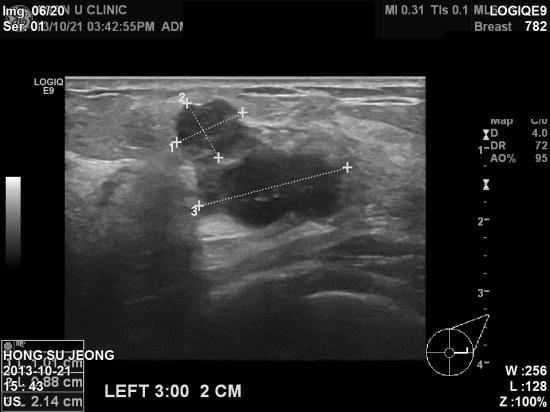

본원에서 초음파 검사결과

좌측유방에 큰 혹을 비롯하여

겨드랑이 임파절까지 전이소견 보였습니다.

좌측유방 조직검사과 겨드랑이

세포검사결과

침윤성 유방암 및 겨드랑이

임파절 전이성 유방암으로 진단되어 치료예정이십니다